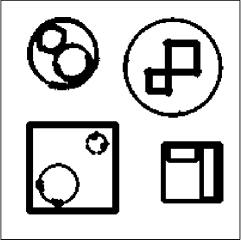

The data (see Figures 1 and 2) was generated in the diffusion model (1.2) using self-written (linear-basis) finite element code in MATLAB. For both examples, we took and used a uniform boundary condition . The simulated data were generated on a -grid and then down-sampled (by averaging) to to avoid inverse crime. After that, Gaussian noise with different intensities (standard deviations of and of the average signal value ) was added to the data.

Reconstruction results and error profiles at different noise levels can be seen in Figures 3 and 4. In both examples, the noise-free reconstructions are very accurate and contain mostly smoothing error. In the low-noise reconstructions, due to the fact that more regularization is necessary, some of the parameter variation is underestimated. In the high-noise examples, most detail in is lost since a lot of regularization is required to get reasonable results. The fine detail in can, however, still be recovered very accurately in both examples.